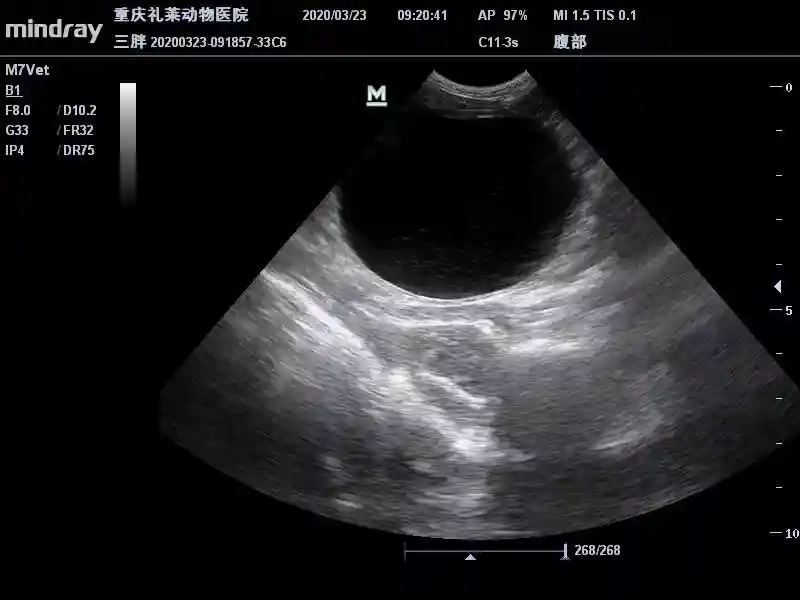

3月23日B超复查膀胱:

膀胱内散在高回声声影减少,膀胱壁光滑。